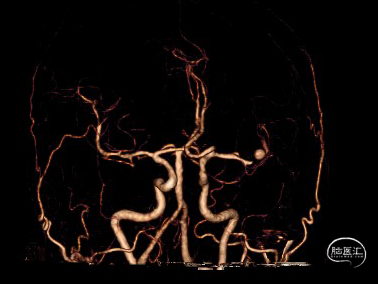

DSA检查提示左侧大脑中动脉上干闭塞

扩张后血管依然闭塞,改用2.0*15mm 球囊,扩张后提示M2段血流通畅,可见动脉瘤大小约4-5mm。

术后即刻影像,M2段远端血流mTICI 3级,动脉瘤内造影剂滞留。